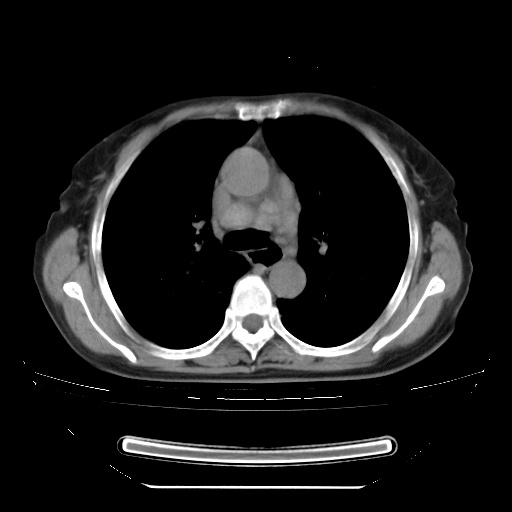

患者女性,72岁,慢性咳嗽3月余,曾抗炎治疗无效果,最近抗结核治疗约半月余,症状缓解。

ct示两肺粟粒状病灶,以两肺上叶尖后段及下叶背段分布为主;首先考虑结核。请战友们分析。

两肺内病灶呈小结节状和树芽状,纵膈的肿大的淋巴结密度不均匀,并见有钙化,考虑为两肺结核可能更大些。

两肺内病灶呈小结节状和树芽状,纵膈的肿大的淋巴结密度不均匀,并见有钙化,多形态病灶,考虑为两肺结核,肝内考虑小囊肿。

片子很好,质量很高,两侧肺门淋巴结肿大并有钙化,两肺弥漫病灶,首先考虑tb并播散,但年龄大了呀(72岁)小细胞肺癌不能除外,如果是肺癌也没什么大的治疗了,建议正规抗结核治疗后复查